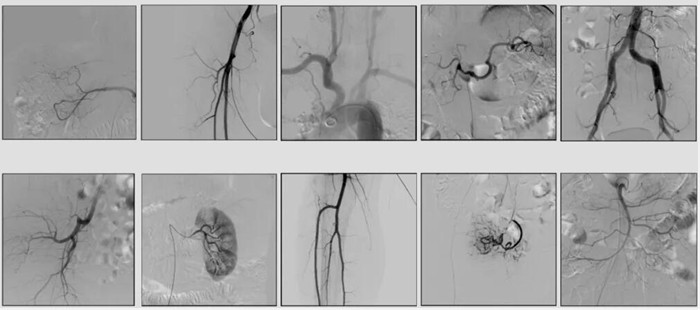

2)中C,學名外周介入C形臂(Peripheral Interventional C-Arm)。與小C相比,中C不僅大幅提高了X射線系統(tǒng)功率,更重要的是增加了減影等血管機相關功能,基本可以完成80%的介入手術需求,主要應用在周圍血管科、消化內(nèi)科、婦科、整形科等領域。

中C在周圍血管領域有重要價值